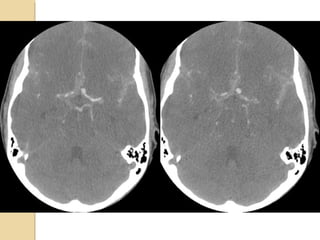

TEMPORAL BONE FRACTURESTEMPORALBONE FRACTURES Look for opacification of the mastoid Longitudinal: 70%, parallel to long axis of petrous bone, conductive hearing loss (from ossicular dislocation), facial nerve paralysis (20%) Transverse: 20%, sensorineural hearing loss, facial nerve paralysis (50%) Complex Complications: meningitis, abscess